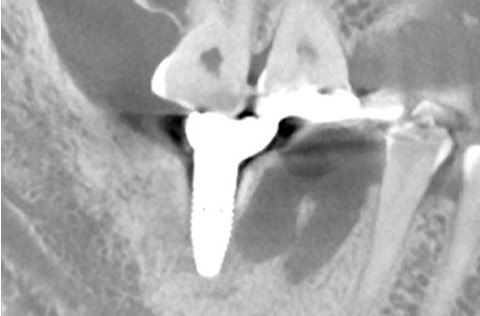

抜歯の6週間後、インプラント埋入と同時に骨造成を行ったケース。じゅうぶんな初期固定が得られた。